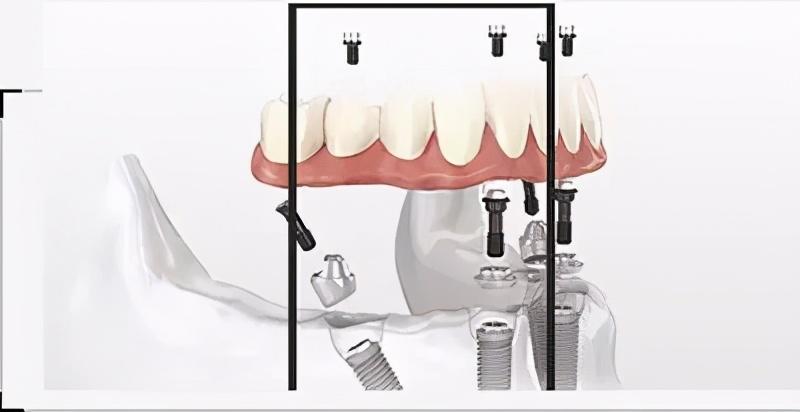

確定能手術(shù)后,才會(huì)診斷取模、制定種植牙方案。(第一次大約1個(gè)多小時(shí))然后正式開始種植牙手術(shù)。在牙槽骨上制備一個(gè)孔,植入人工種植體。將牙骨床內(nèi)嚴(yán)密縫合,大約一個(gè)星期后可以拆線(這次大概7--10天)。

注明:此植體只是模擬位置,不做確切種植位置。